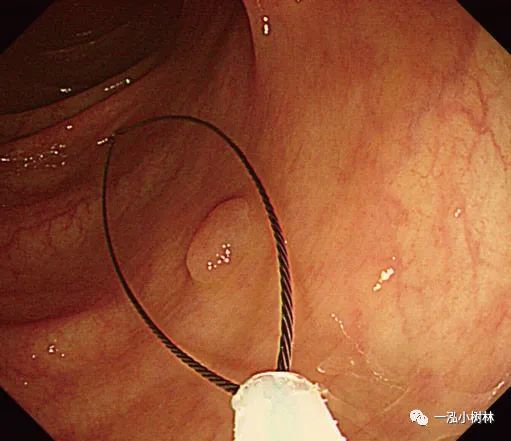

图5a 横结肠处4mm大小0-IIa型腺瘤

图5b 在病灶上方圈套

图5c 圈套包括病灶周围1-2mm正常黏膜

图5d 对病变进行机械性横切

图5e 对病变进行机械性横切

图5f 息肉取出后出血

图5g 黏膜出血止血

图5h 可见息肉边缘正常黏膜的标本